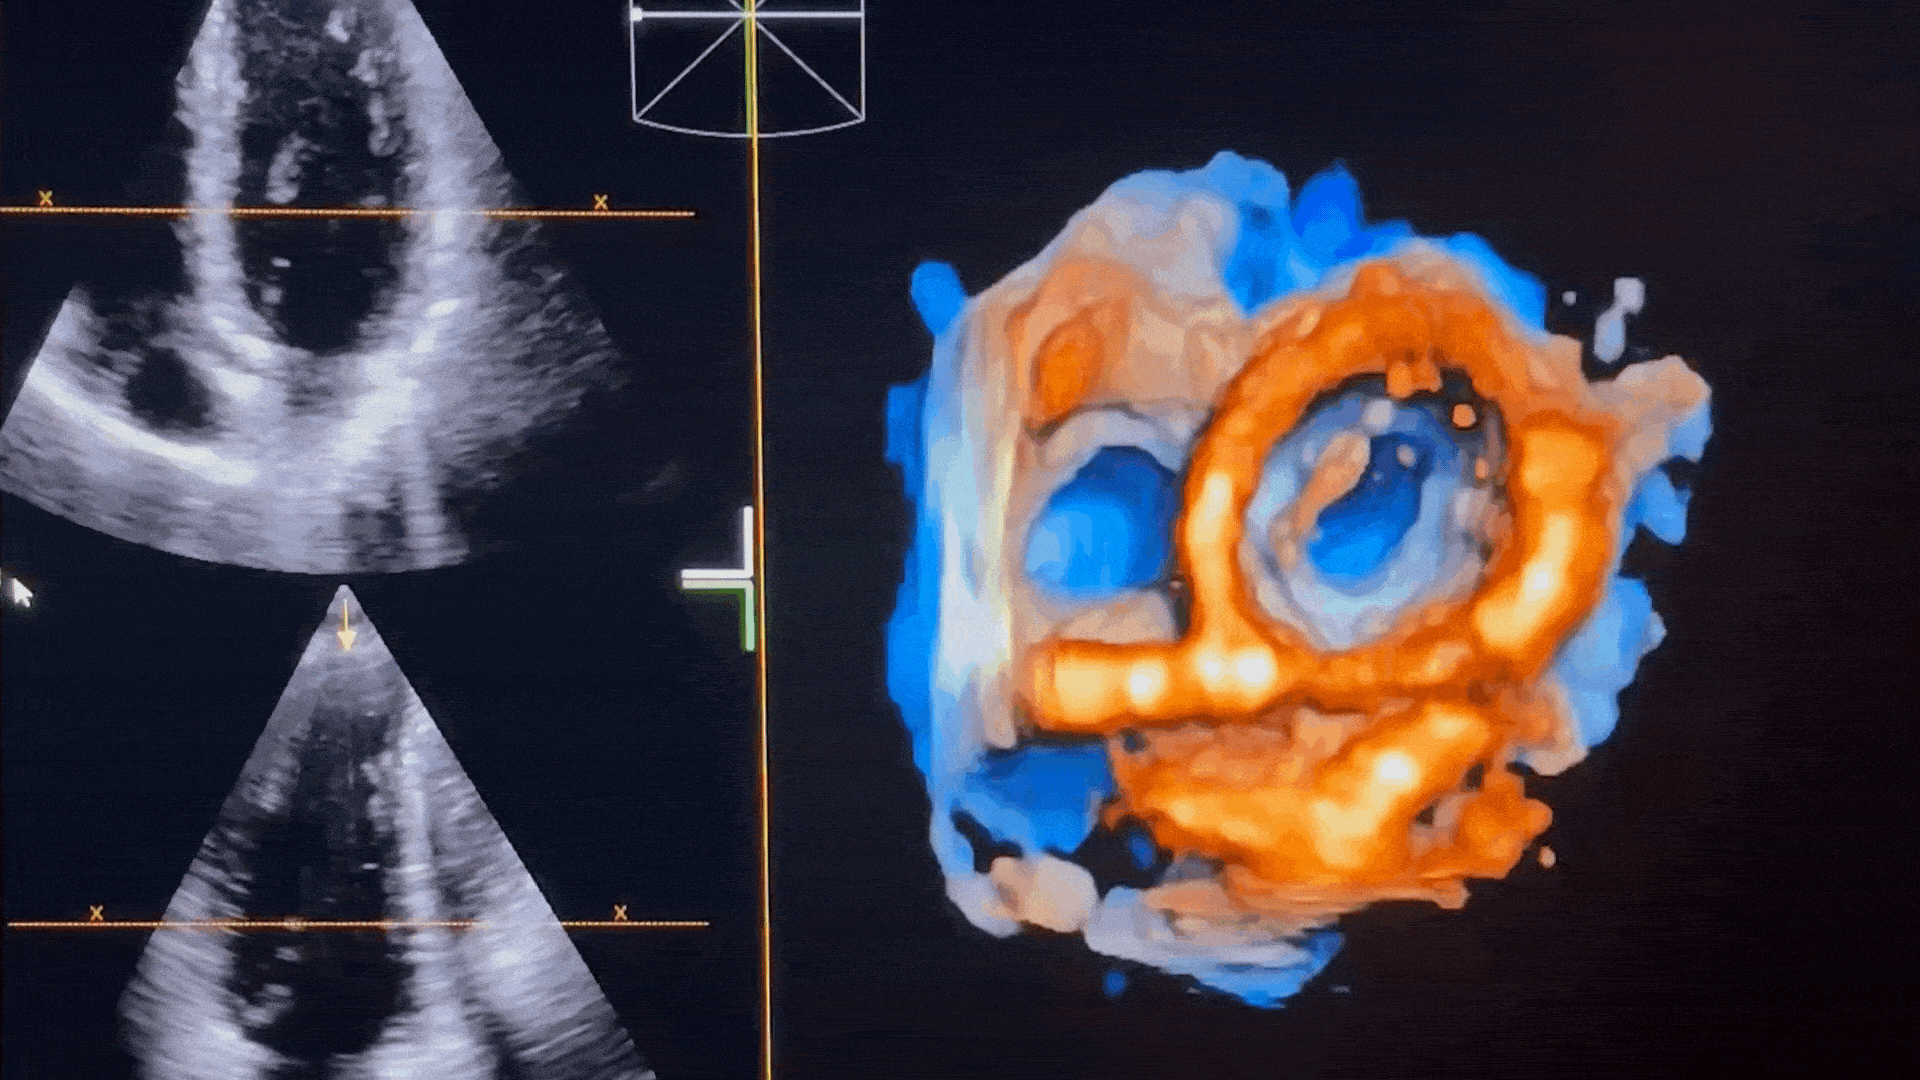

Cette formation immersive de 2 jours à Paris combine enseignement théorique, ateliers pratiques sur échographes et utilisation de modèles de démonstration. Encadré par un deux IPA experts titulaires du DIU d’échographie, ce week-end propose une progression structurée : apprentissage des coupes de référence, maîtrise des mesures fondamentales, analyse hémodynamique et intégration clinique des données.